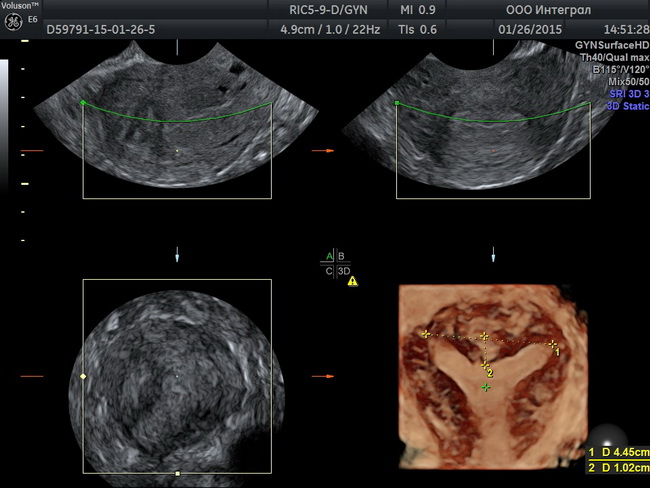

Гинекологическое узи

Университетская клиника «Я здорова!» проводит узи органов малого таза в Москве. Гинекологическое узи проходит безболезненно. После процедуры пациент получает подробный протокол с описанием диагностических данных. Ознакомиться с процедурой более подробно Вы можете на нашем сайте

Гинекологическое